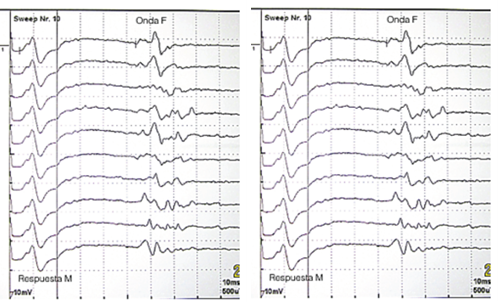

Figura 2. Representación de la latencia de la onda F en el nervio peroneo izquierdo y derecho, en nuestro paciente. Mostrar/ocultar

- Ondas F: onda F del nervio tibial posterior derecho e izquierdo con valores neurofisiológicos normales. Ligero aumento de la latencia de la onda F del nervio peroneal izquierdo –raíz L5, plexo lumbo-sacro– (59,2 ms, normal <56,7 ms). Onda F de nervio peroneal derecho con valores neurofisiológicos normales (Figura 2).

La onda F es un potencial motor pequeño que aparece tardíamente en relación con el potencial de acción o respuesta M, tras la estimulación de un nervio periférico. Su origen obedece a la despolarización directa de las motoneuronas del asta anterior de la médula espinal, a consecuencia del impulso antidrómico que alcanza el cono axónico a partir del sitio de estimulación (Figura 3). Permite evaluar la porción proximal del axón motor. Es útil en la evaluación de los nervios largos y es un indicador de lesión periférica, especialmente de localización proximal, lo cual permite diferenciar una lesión de la raíz nerviosa de una lesión periférica distal3. Es útil en neuropatías proximales o en aquellas en donde de forma temprana no es posible obtener mayor información del segmento proximal, por ejemplo, síndrome de Guillain Barré y en radiculopatías. Si se ajusta el valor de la latencia de la onda F con la longitud de la extremidad, un valor que supere dos desviaciones estándar se puede considerar anormal.